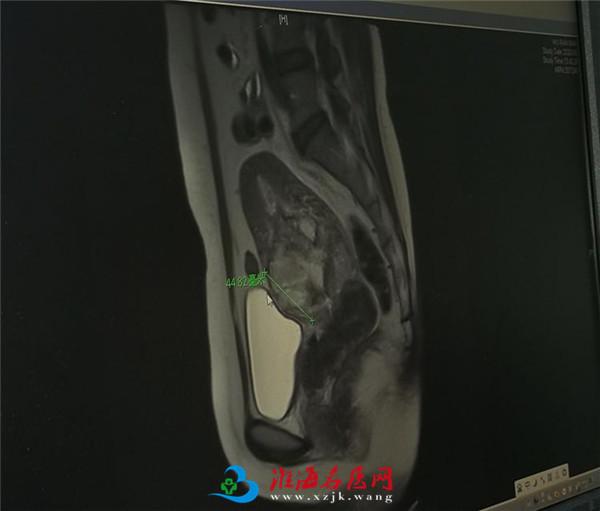

根据核磁共振检查,妇产科专家们进行了讨论,胎盘植入比较明确,而且有穿透性植入可能,采用保守方法还是手术方法治疗?如果手术治疗,一是子宫切除可能性极大,二是手术难度很大,输尿管,膀胱损伤可能性也大,与彭先生沟通过程中,他表示媳妇尚年轻,要求尽力保子宫。